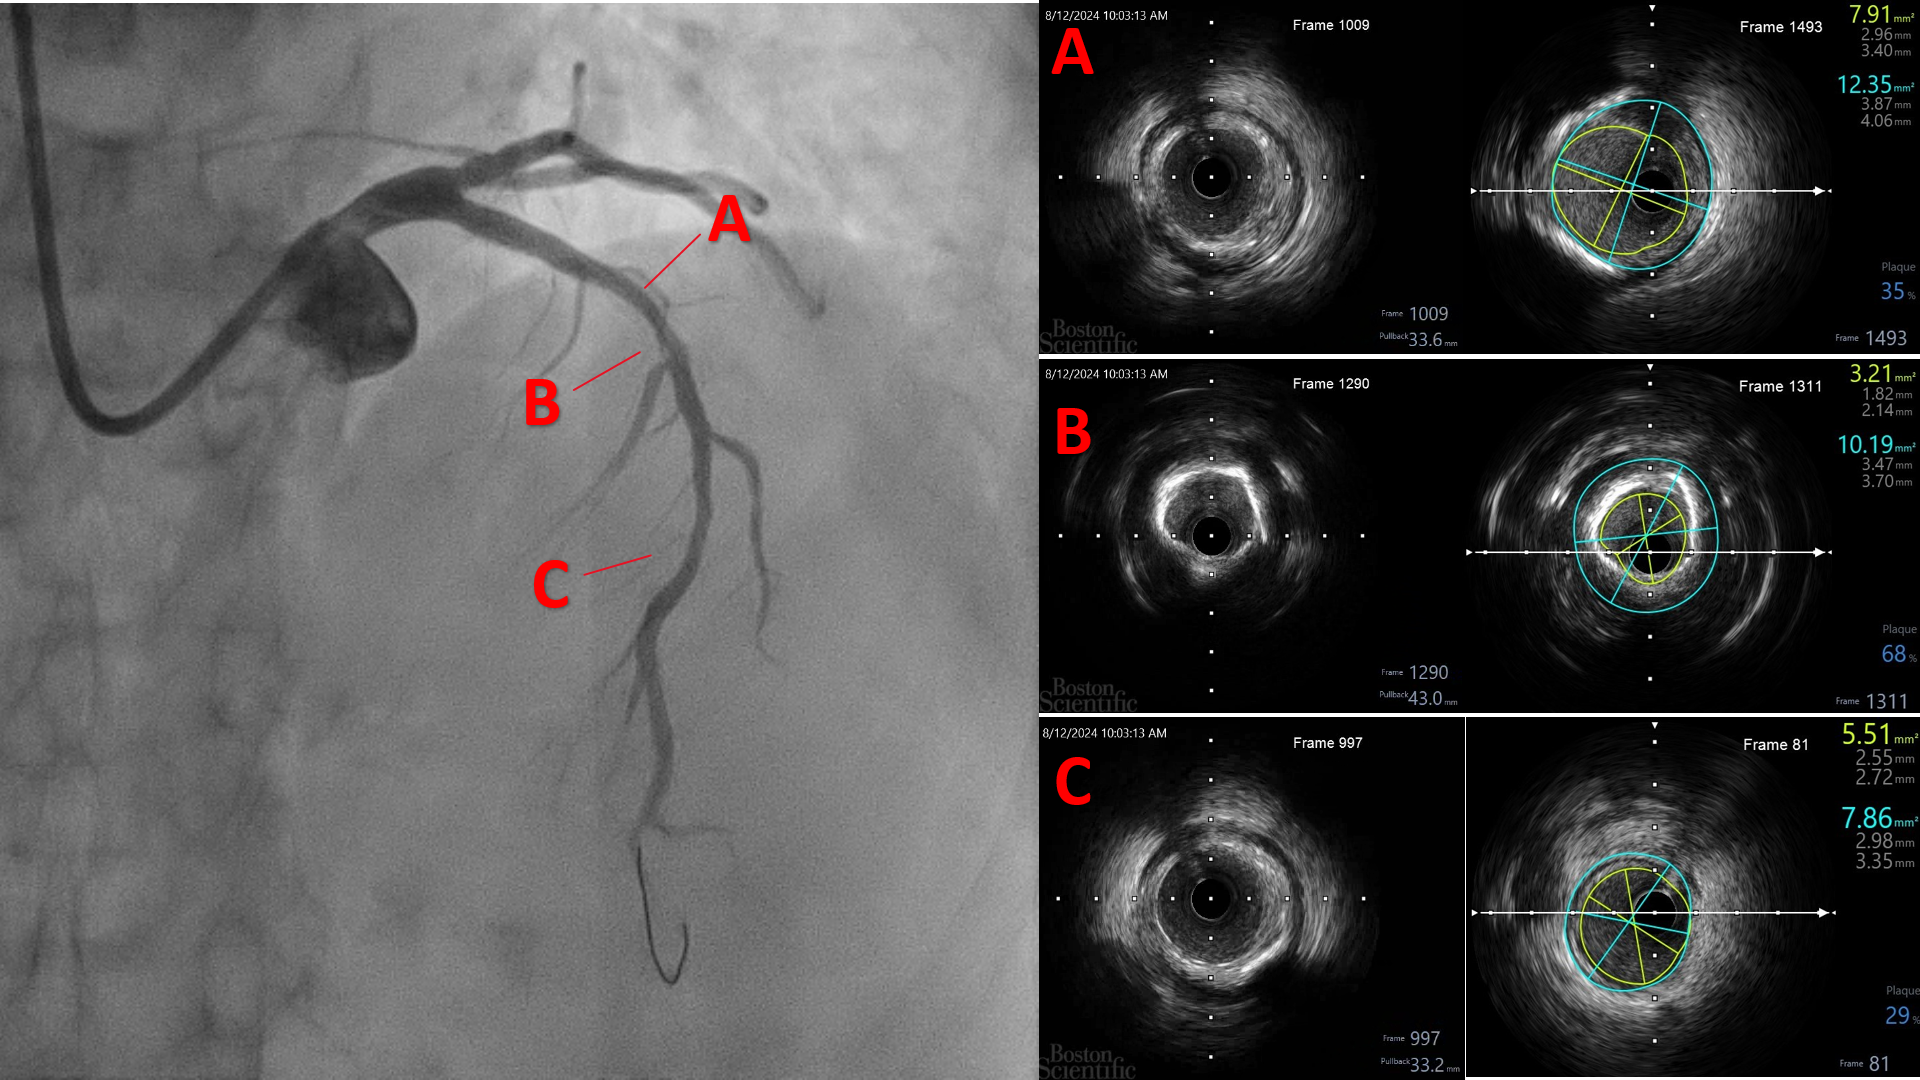

The procedure was performed using a 7 Fr right radial approach. A total of 6000 units of intracoronary heparin and 300 mg of oral clopidogrel were administered. The left coronary system was engaged with a 7 Fr extra-backup (EBU) 3.5 mm guiding catheter, and the lesion was successfully crossed with a Run-through floppy wire extending to the distal LAD. Pre-dilation was performed with a 2.0 mm x 15 mm Genoss balloon, inflated to 16 atm. Intravascular ultrasound (IVUS) imaging revealed 360-degree superficial calcium at the tight LAD lesion, a vessel diameter under 3.5 mm, and a calcium score of 2. The mid-LAD measured 3.0 mm and the proximal LAD measured 4.0 mm. Pre-dilation was performed in the mid-LAD using a 3.0 mm x 16 mm Genoss non-compliant (NC) balloon, and in the proximal LAD with a 3.5 mm x 20 mm NC Emerge balloon, both inflated to 16 atm. Post-pre-dilation IVUS imaging showed cracking of the superficial calcium with vessel expansion to 3.0 mm. Subsequently, drug-coated balloon (DCB) angioplasty was performed with a 3.0 mm x 30 mm Magic Touch DCB in the mid-LAD and a 3.5 mm x 35 mm Magic Touch DCB in the proximal LAD. Final angiography demonstrated a non-flow-limiting Type A dissection with less than 30% recoil, and the procedure was successfully concluded.